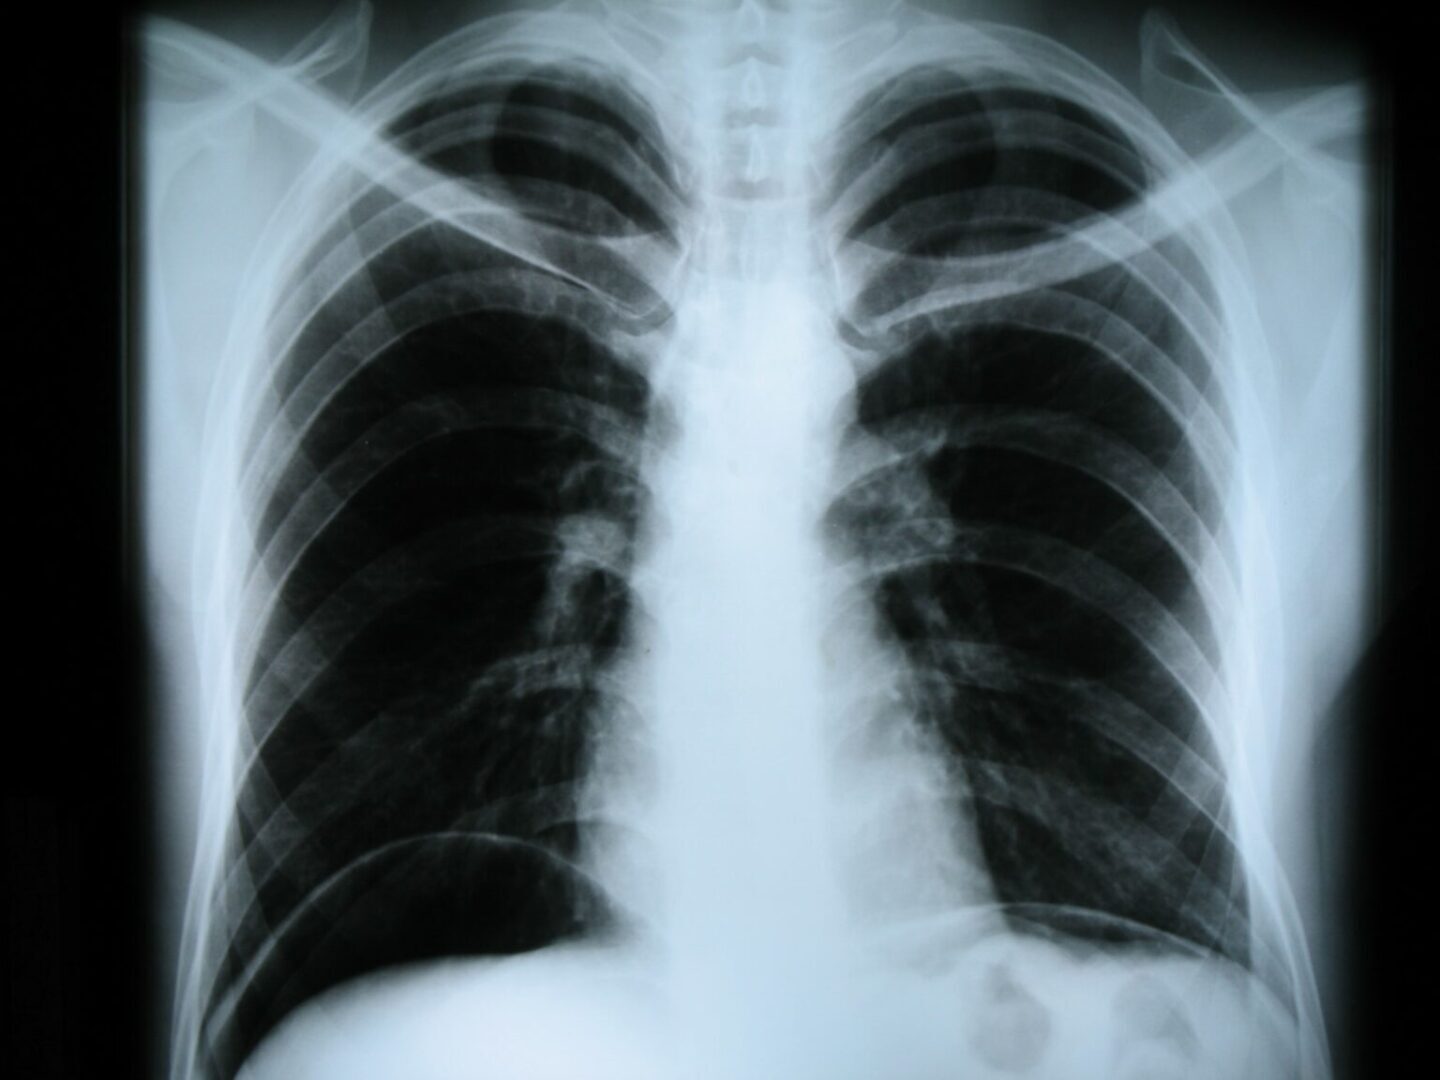

Рентгенограмма органов грудной клетки в прямой проекции. Видно скопление воздуха под куполами диафрагмы